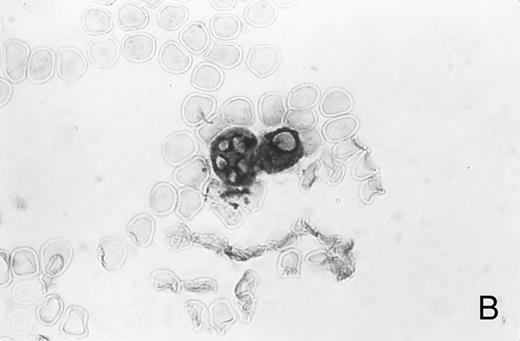

Immunocytochemistry of blood and BM. (A) Blood smear from a healthy donor stained with MoAb AAA4 shows NAMLAA-positive granulocytes and an NAMLAA-negative monocyte (arrow). (B) BM smear after staining with AAA4 shows an NAMLAA-positive promyelocyte and a mature granulocyte, both NAMLAA-positive.

Immunocytochemical studies of blood and BM showed that granulocytes, but not monocytes, stained positive for NAMLAA (Fig 1A). Figure 1B shows that band-form granulocytes from BM were also positively stained for NAMLAA. Although monocytes and spleen macrophages did not express NAMLAA, a 20% subpopulation of highly fluorescent bronchoalveolar macrophages was positive for NAMLAA (Fig 2), indicating that differentiation of monocytes to macrophages induces NAMLAA expression.